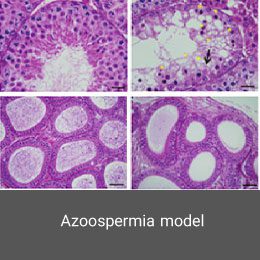

- Create and induce a variety of animal models